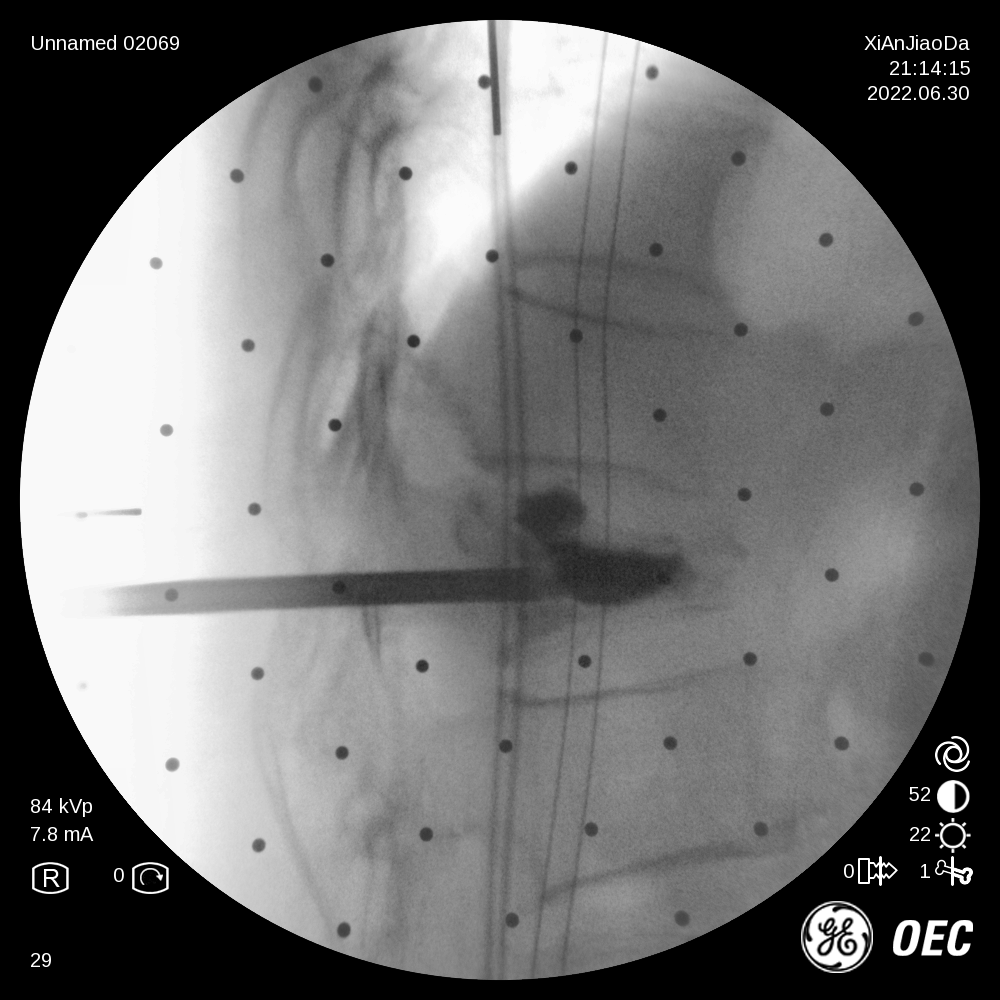

6月30日,骨关节外科成功为一例复杂椎体压缩性骨折病人在局麻下行机器人辅助经皮椎体球囊扩张成形术。在王坤正主任的指导下,宋金辉副主任医师、张晨副主任医师借助机器人术前规划与术中辅助,快速高效完成了该手术,患者取得满意疗效。

患者为一69岁女性,6月前摔倒后出现腰部疼痛伴活动受限,保守治疗后效果不佳遂来我院,经过诊断分析,该患者椎体重度压缩性骨折,重度骨质疏松致透视下骨性标志不明显,且存在轻微脊柱侧弯。王坤正主任团队最终决定运用智能化的手段,在局麻下行机器人辅助经皮椎体球囊扩张成形术,采取直观定位技术,相较其他机器人的定位导航技术,无需定位标志物,使得手术能够在全程局麻下操作,保证医生能得到患者的实时反馈,可使手术更精准、更便捷、更安全。

术前,王坤正主任团队采集患者的三维CT数据并将其导入到机器人术前规划系统中,机器人工程师与其配合确定穿刺位置、角度、深度等信息,制定出适合患者本人的个性化手术方案并在术中由机器人予以实施。

在该机器人辅助手术过程中,仅需通过正侧位进行伤椎识别,通过软件将正侧位透视图与术前规划数据的结合,即可得到病人伤椎的姿态以及实际的穿刺角度,之后机械臂根据软件参数进行精准定位,手术医生在机械臂引导下一次性进针成功,并对进针位置角度表示满意,整个过程少于20分钟,实现了手术的更精准化、高效化。相较于传统定位流程,术前规划只能保存在医生脑海中,术前与术中流程无法很好的衔接,术中穿刺依赖医生丰富的经验,对于情况复杂的病人,术中需要反复试验,导致手术时间延长、患者受辐射量增加。后续放置球囊、注入骨水泥等操作则同传统手工操作。